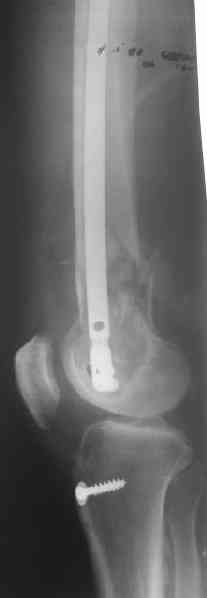

Удалили ластину без проблем. Выявилась значительная подвижность. В этих условиях сразу пропала мотивация к постепенной коррекции аппаратом. Попробовал восстановить длину, введя между отломками spreader. Отчасти удалось. Тогда защили рану, наложили спицевой дистрактор (2 спицы в дистальный отдел и 1 вверху). после этого был убран и спонгиозный винт. И сделали антгерадное штифтование, как говорится, "по принятой в

клинике методике".

С.Максимов:

> При остеосинтезе гвоздем кроме доступа для удаления пластины и

> репозиции необходим дополнительный доступ и дополнительная травма

> сустава (?).

Дополнительные доступы для введения гвоздя и проксимальных винтов понадобились, но они маленькие, по 1 см. Нижние винты ввели прямо между швами. Суставы дополнительно не травмировали, и даже ввели гвоздь не через f. piriformis, а через большой вертел.

Длину восстановили, возможно, даже с изьбытком, ну да динамизируем пораньше. Введенные в овальное отверстие дистальые винты имеют угловую стабильность. Снимки приложены. Заранее спасибо за критику и комментарии.